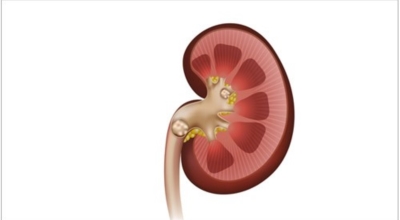

요로결석이란

수분 섭취 감소는 요로결석의 가장 주요한 발병 이유가 되는 것 이라고 하네요. 수분의 섭취가 떨어지면 요석결정이 소변에 머무르는 시간이 길어져 요석형성이 증가하게 되며 요로결석의 발생은 유전적인 소인이 있다는 것이 정설이나 후천적인 생활습관도 연관성을 보입니다.

남성이 여성에 비교해 2-3배 발생 위험성이 높고, 20~40대의 젊은 연령층에서 잘 발생하였다고 하나 최근 고령층에서 발생이 증가하고 있고 요로결석은 지리적으로 산이 많은 지역, 사막, 열대 지방에서 많이 생기는데, 이는 음식, 온도, 습도 등이 복합적으로 작용하기 때문이라고 합니다. 온도와 계절은 요로결석 발생에 주요한 요인으로 작용하지만, 여름에는 땀을 많이 흘리면서 소변이 농축되어 요로결석의 생성이 용이해진다고 합니다.